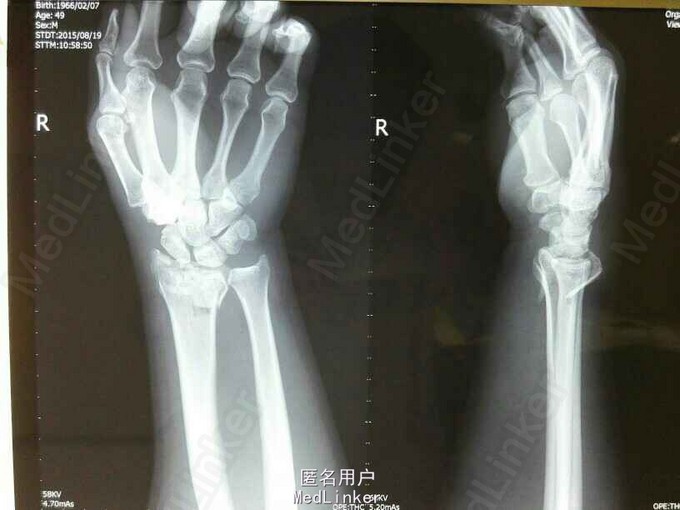

主诉:摔伤右腕部肿痛,活动受限2小时。 病史:2小时前摔伤致右腕肿胀,疼痛,活动时疼痛加重,无右手皮肤麻木,未经处理,来我院就诊。

查体:右腕部畸形,肿胀,压痛,活动受限,右手各指皮肤触痛觉无减退,肌力正常。 拍片示:右桡骨远端粉碎性骨折。

诊断:右桡骨远端粉碎性骨折。 治疗:暂予石膏托固定,五天后右腕部肿胀明显消退,在臂丛麻醉下行右桡骨远端骨折切开复位克氏针+外固定支架固定术。术后复查片见骨折对位对线良好,各指皮肤触痛觉无减退,活动可。